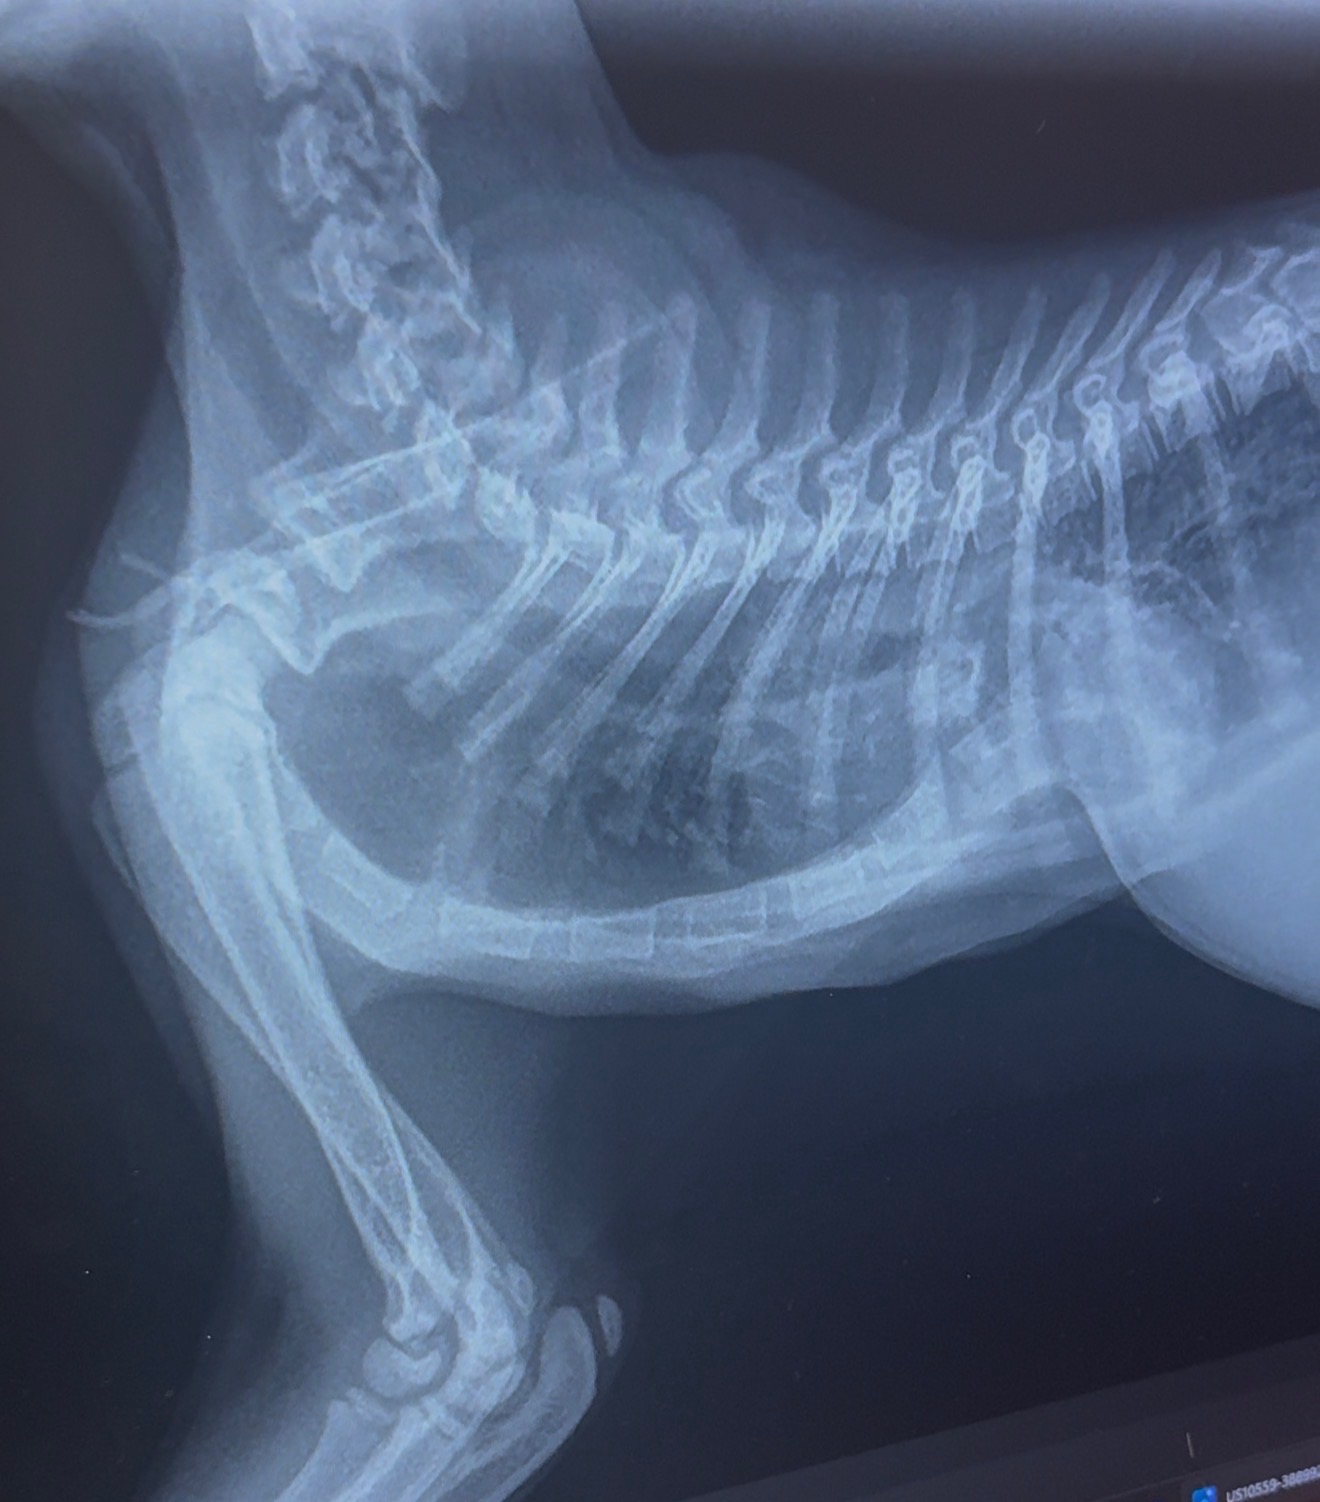

Frankie was diagnosed with severe Pectus Excavatum, a congenital condition where the chest wall caves inward and compresses the heart and lungs. In Frankie’s case, it’s affecting her ability to breathe normally, and her veterinary team has recommended urgent corrective surgery to give her a chance at a full, healthy life.

Because her chest is still developing, this surgery needs to happen ASAP. Waiting could mean her lungs and heart don’t have room to grow… or worse.